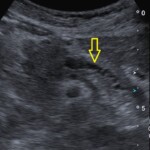

② 直接見えなくても「間接所見」から気づける場合

腹部エコーの大きな強みは、膵臓がんを直接見えなくても、間接的なサインを捉えられる点にあります。

膵臓癌が膵管を圧迫・閉塞すると、

膵管の拡張など、膵臓の管の変化が起きます。

といった変化が起こります。これらは腹部エコーで比較的見つけやすい所見です。

「膵臓がんそのものははっきり見えないけれど、膵管が太くなっている」といった変化は、

膵臓に何らかの異常がある重要なサインです。

この段階で異常に気づくことが、早期発見につながることがあります。

@膵がん 膵管拡張